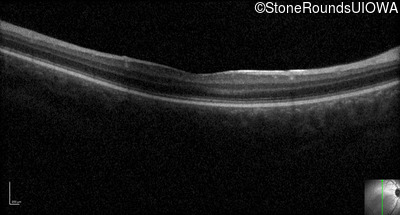

Optical Coherence Tomography - Right - 10/125 -1

Exemplar / OCT Stack

OCT Stack

Optical Coherence Tomography - Left - 10/100 -1